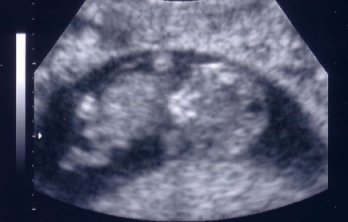

A pénteki UH előtt én teljesen beparáztattam magam, és már felkészítettem magam a legrosszabbra, mert a múlt héten egyfolytában mindjárt-megjön érzésem volt, közben semmi kismami-tünet (se cicifeszülés, se hasszurkálás, róka-komának meg végképp se híre se hamva…). Na, meg megnéztem egy mérettáblázatot, hogy amikor az UH lesz, már majdnem 3 centisnek kell lennie a babucinknak, ehhez képest kiderült, hogy csak 2,54... Később persze rájöttem, hogy az a mérettáblázat, amit néztem, az ausztrál populációra vonatkozik, és a magyar átlagok alapján a gép 9+4 napos terhességnek becsülte, pont amennyi pénteken voltam! Úgyhogy nagyon elszégyelltem magam, hogy ennyit aggodalmaskodtam meg egy kicsit elégedetlenkedtem

, miközben ő gyönyörűen fejlődik!

De aztán amikor Apánk felém fordította a képernyőt, azt hittem, hogy elolvadok! A babócánk folyamatosan ficánkolt, integetett a kis kezeivel, látszott, hogy nagyon jól érzi magát odabent! Hát, azóta mi is lubickolunk a boldogságban, nemcsak ő!